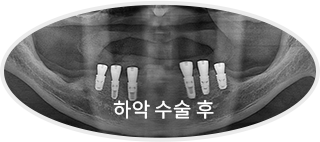

All-on-x는 4~6개의 임플란트만으로

전체 치아를 지지하는 방식으로 진행됩니다.

기존 전체 임플란트 대비 식립 개수를 줄이면서도

안정적인 지지력을 확보할 수 있어

틀니의 불편함 없이 자연스러운 저작이 가능합니다.

치료 후 사진

[ 환자분의 동의서 작성 후 게시하였습니다 ]